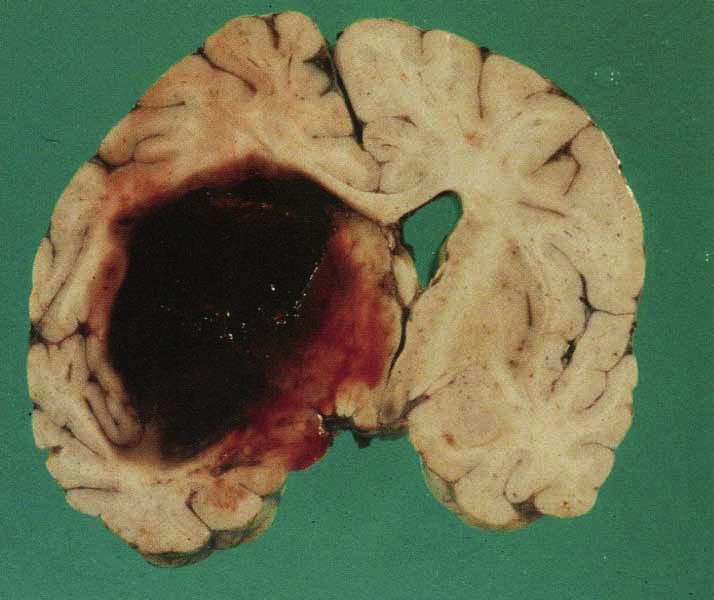

Hypertensive intracerebral hemorrhage

Basal ganglionic hemorrhage & rupture into ventricular system